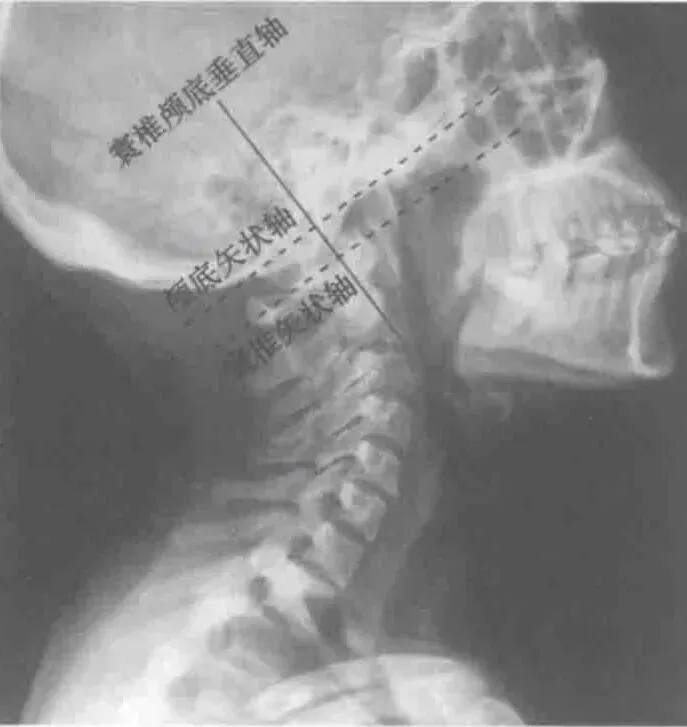

寰枕关系是寰椎与颅底骨面之间的空间关系。

正常情况下,寰椎纵轴与颅底呈现垂直关系,即寰椎的前弓、后弓与颅底的空间距离近似相等,这样能使延髓下段和颈髓上段的运动空间最大化。影响头颅的空间位置的肌肉中,后伸肌群的抗重力作用最大,肌力大于前屈肌群。当后伸肌群过度兴奋或出现黏弹性紧张时,寰枕后间隙变窄的情况明显增多。寰枕后间隙变窄造成延髓压力增高,出现神经调节障碍的多种症状,如肢体位置觉和运动协调性的改变。寰枕前间隙的增加,导致其前方软组织出现过多牵拉。寰椎横突前方有交感神经链上的第一个神经节-颈上神经节、迷走神经、舌咽神经、副神经和颈内静脉。寰枕前间隙增宽时,上述结构受到牵拉靠近寰椎横突,扭转头部动作直接造成挤压刺激出现相应症状。